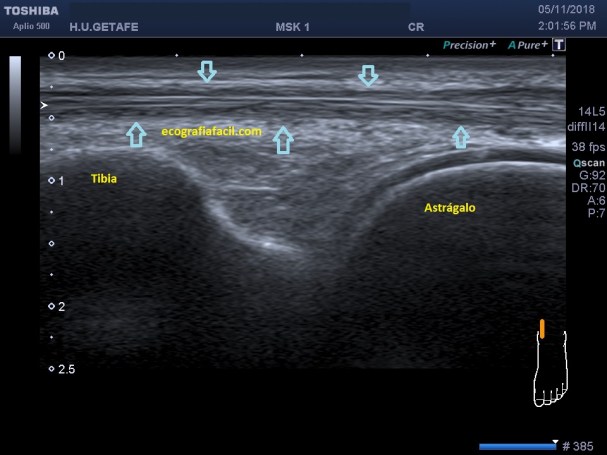

Esta imagen es preciosa, está tomada en longitudinal como muy bien sabes, justo en la articulación de la tibia con el astrágalo, es fino y potente e inicia su descenso hacia la cara interna del pie para insertar.

El Tibial Anterior es un tendón fuerte, fácil de localizar en la cara anterior de la tibia, ojo con los tendones que pueda ir cerca…

Es hiperecogénico, potente, más pequeño que el Tendón Tibial Posterior y de acceso fácil, comparte espacio con otros tendones, pero suele ser sencillo de visualizar y seguir.